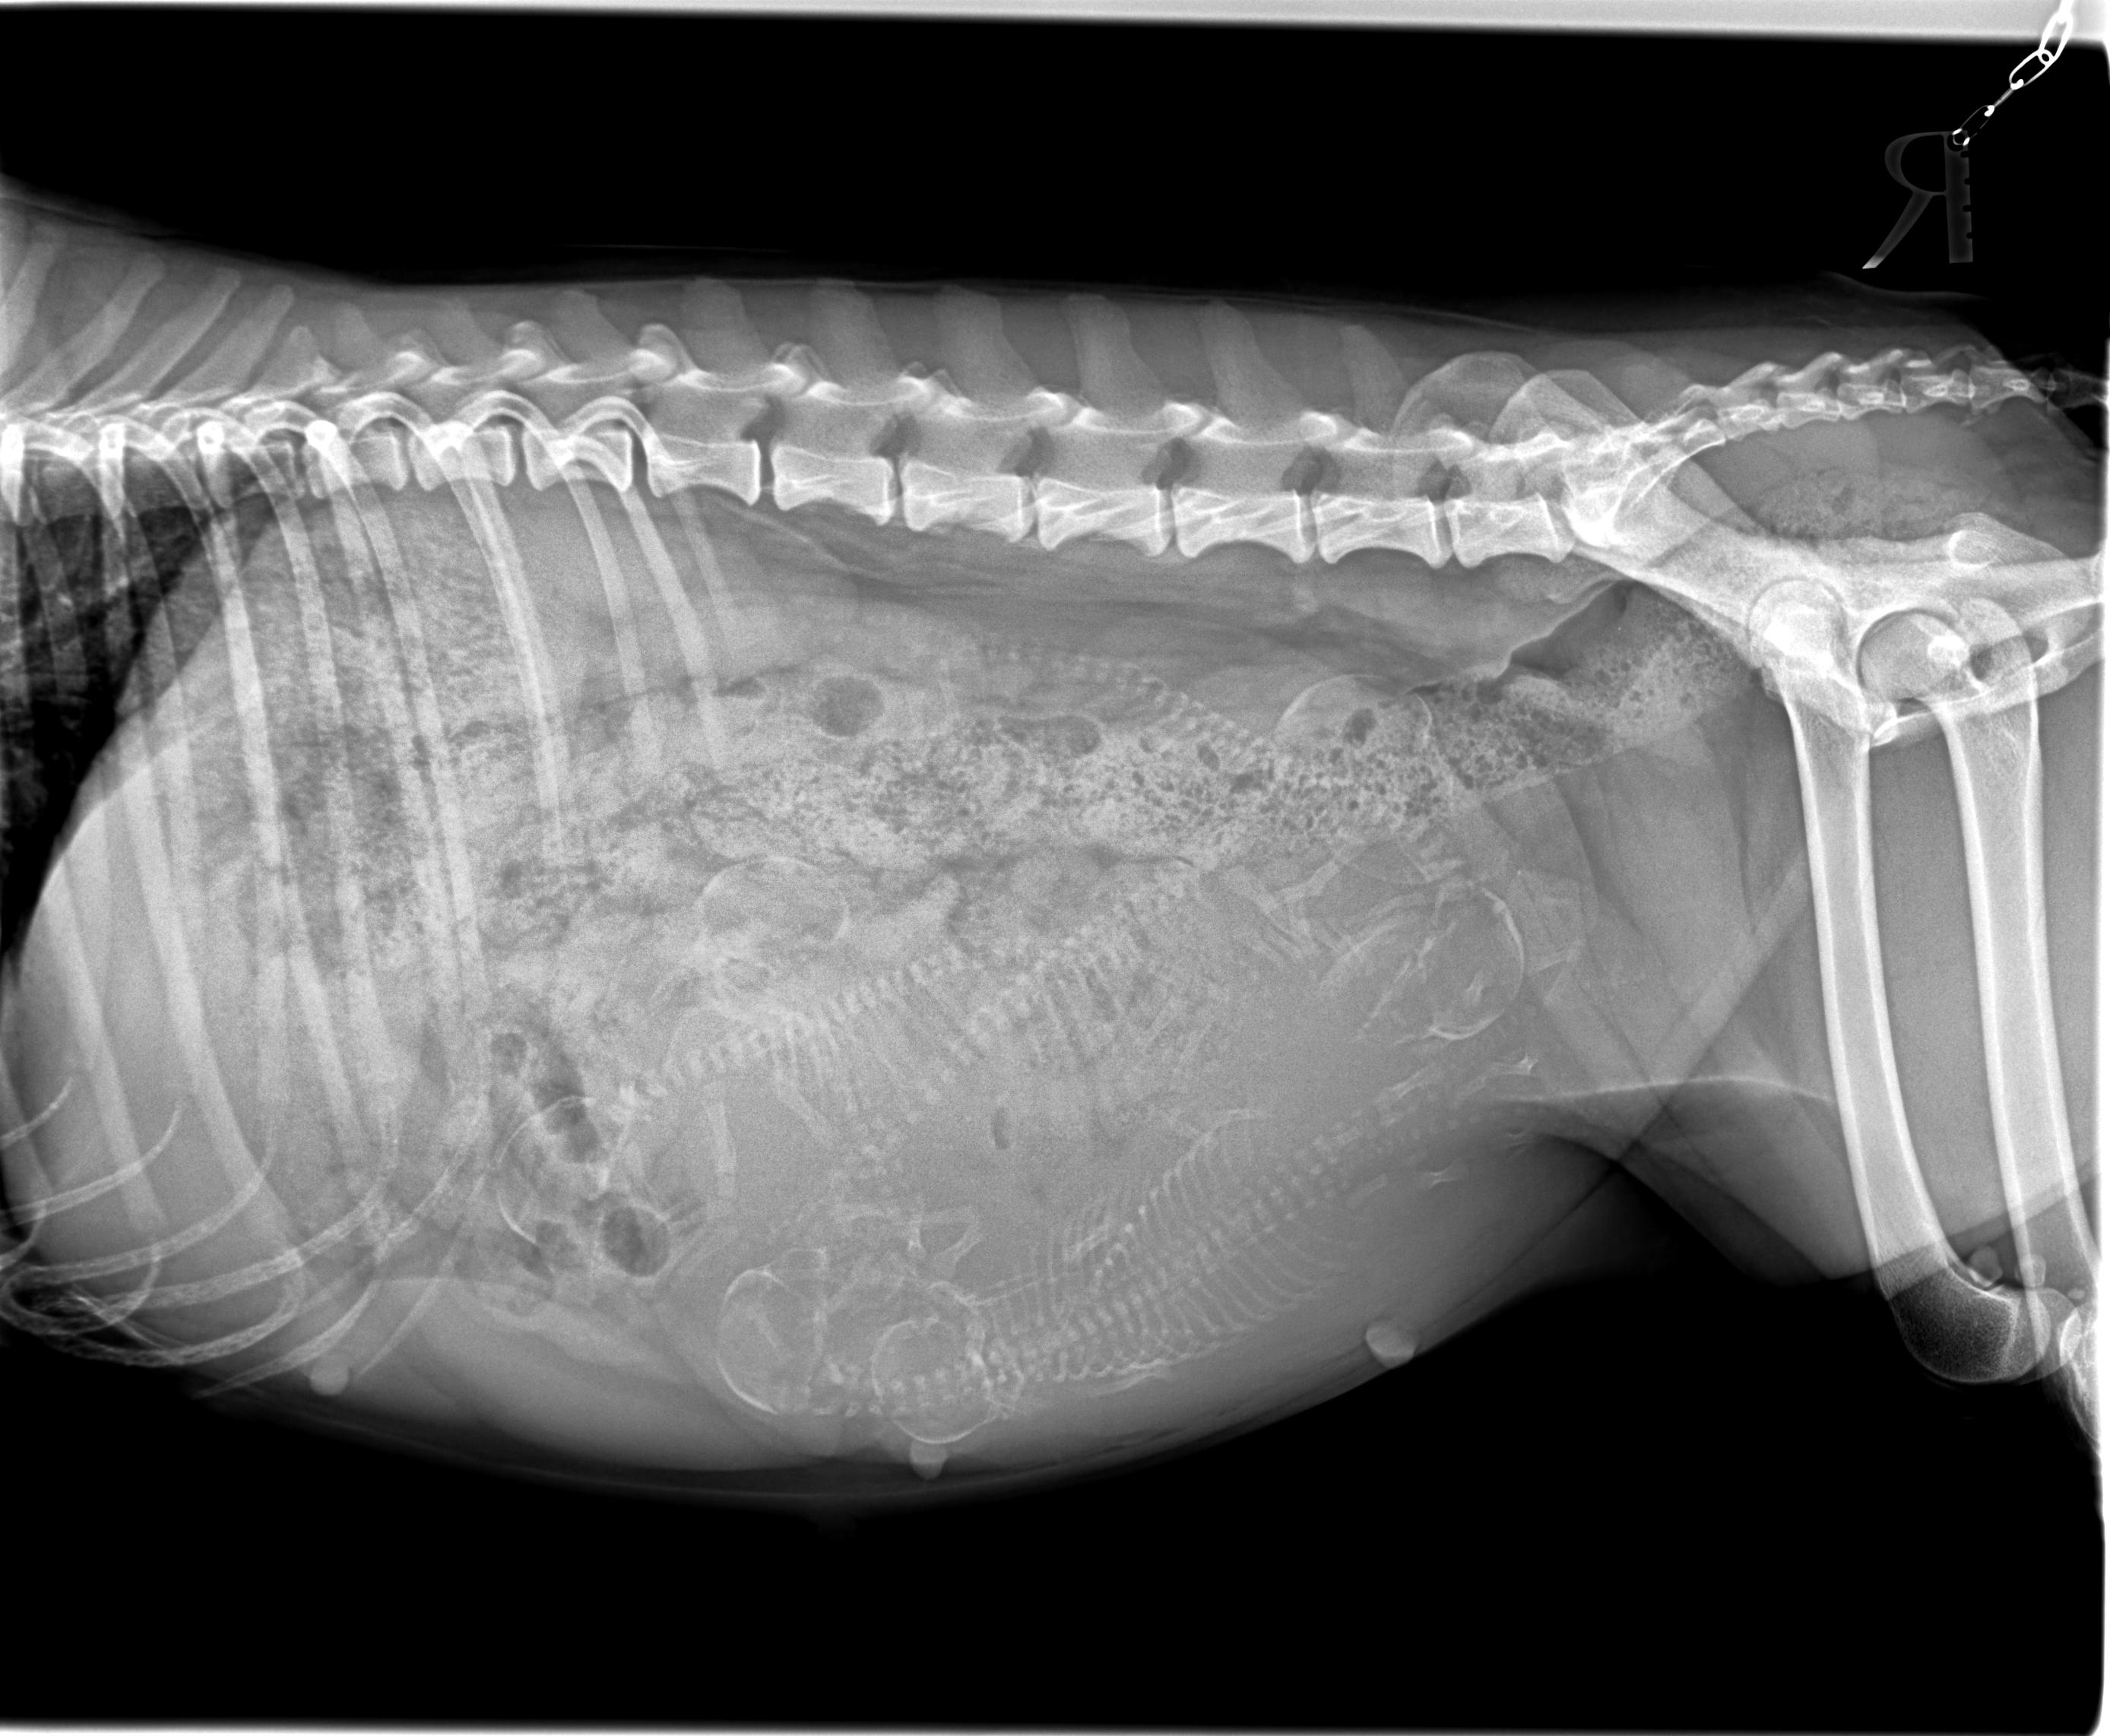

Am 26.01.2023 waren wir mit Coco zum Röntgen und es wurden sechs Welpen erkannt bzw. dargestellt. Das Röntgenbild ist unten ersichtlich und jeder kann einmal selber sein Glück beim Zählen versuchen. Wir sind sehr froh, dass es diesmal keine 10 Welpen werden, so wird die tolle Welpenzeit für die Mutter und uns als Züchter wesentlich entspannter.